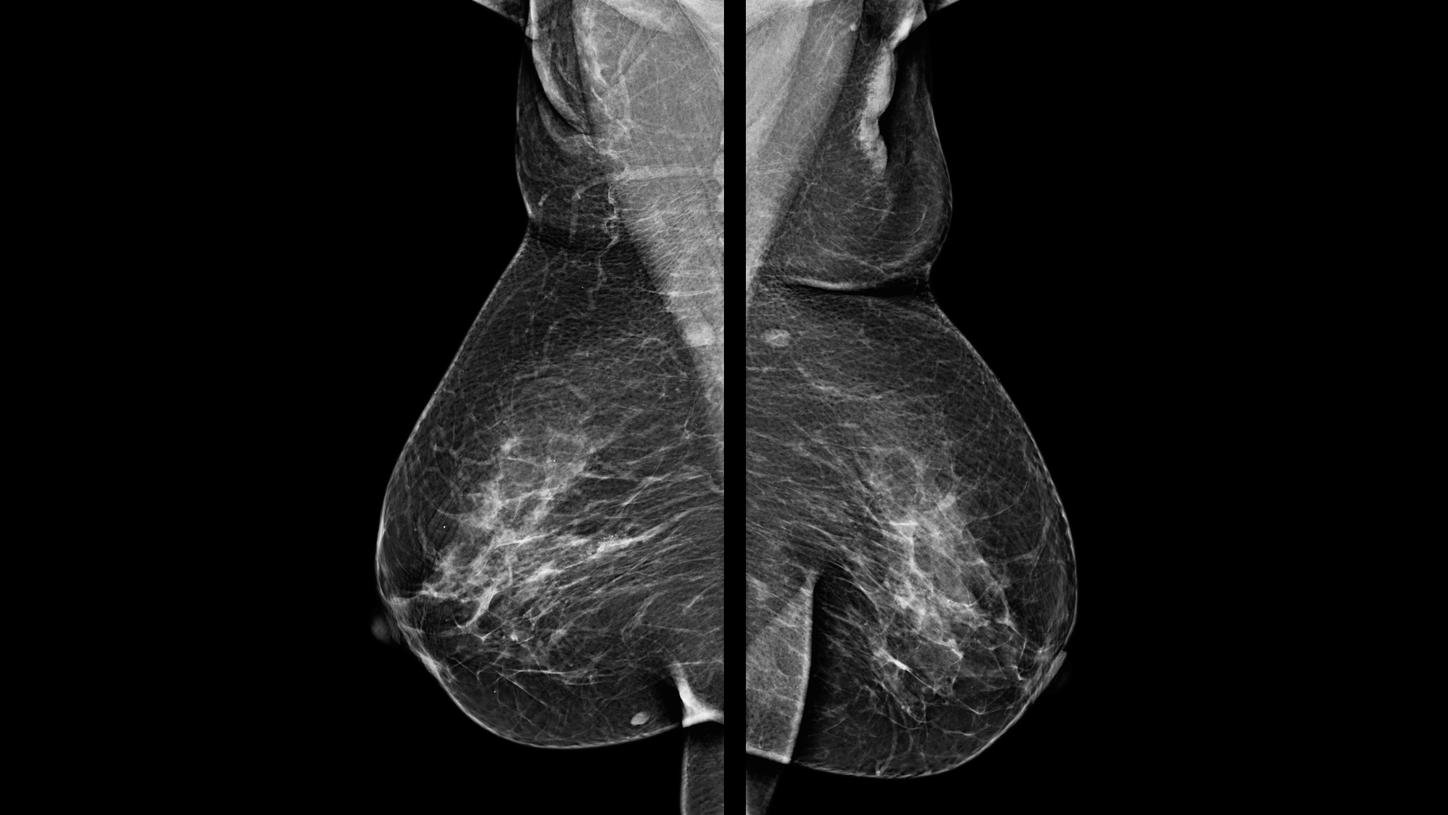

Paciente assintomática de 48 anos, realizou mamografia de rastreio (imagem 1 e 2) que evidenciou um pequeno grupamento de microcalcificações com morfologia pleomórfica e distribuição segmentar, localizado na UQM (união dos quadrantes mediais) da mama direita, não disponibilizou exames anteriores e retornou ao mastologista que solicitou core-biópsia por estereotataxia.

Para atingir os objetivos propostos da core-biópsia por estereotaxia na paciente foi utilizado o aparelho de mamografia da Siemens Healthineers MAMMOMAT Fusion com biópsia estereotáxica. A paciente estava sentada e antes do procedimento foi realizada antissepsia e anestesia local com xylocaína a 2% sem vasoconstritor, o instrumento utilizado para a coleta de fragmentos foi pistola automática com agulha de 14G por 10,0 cm. O material adquirido foi enviado para a análise patológica em um frasco com formol.